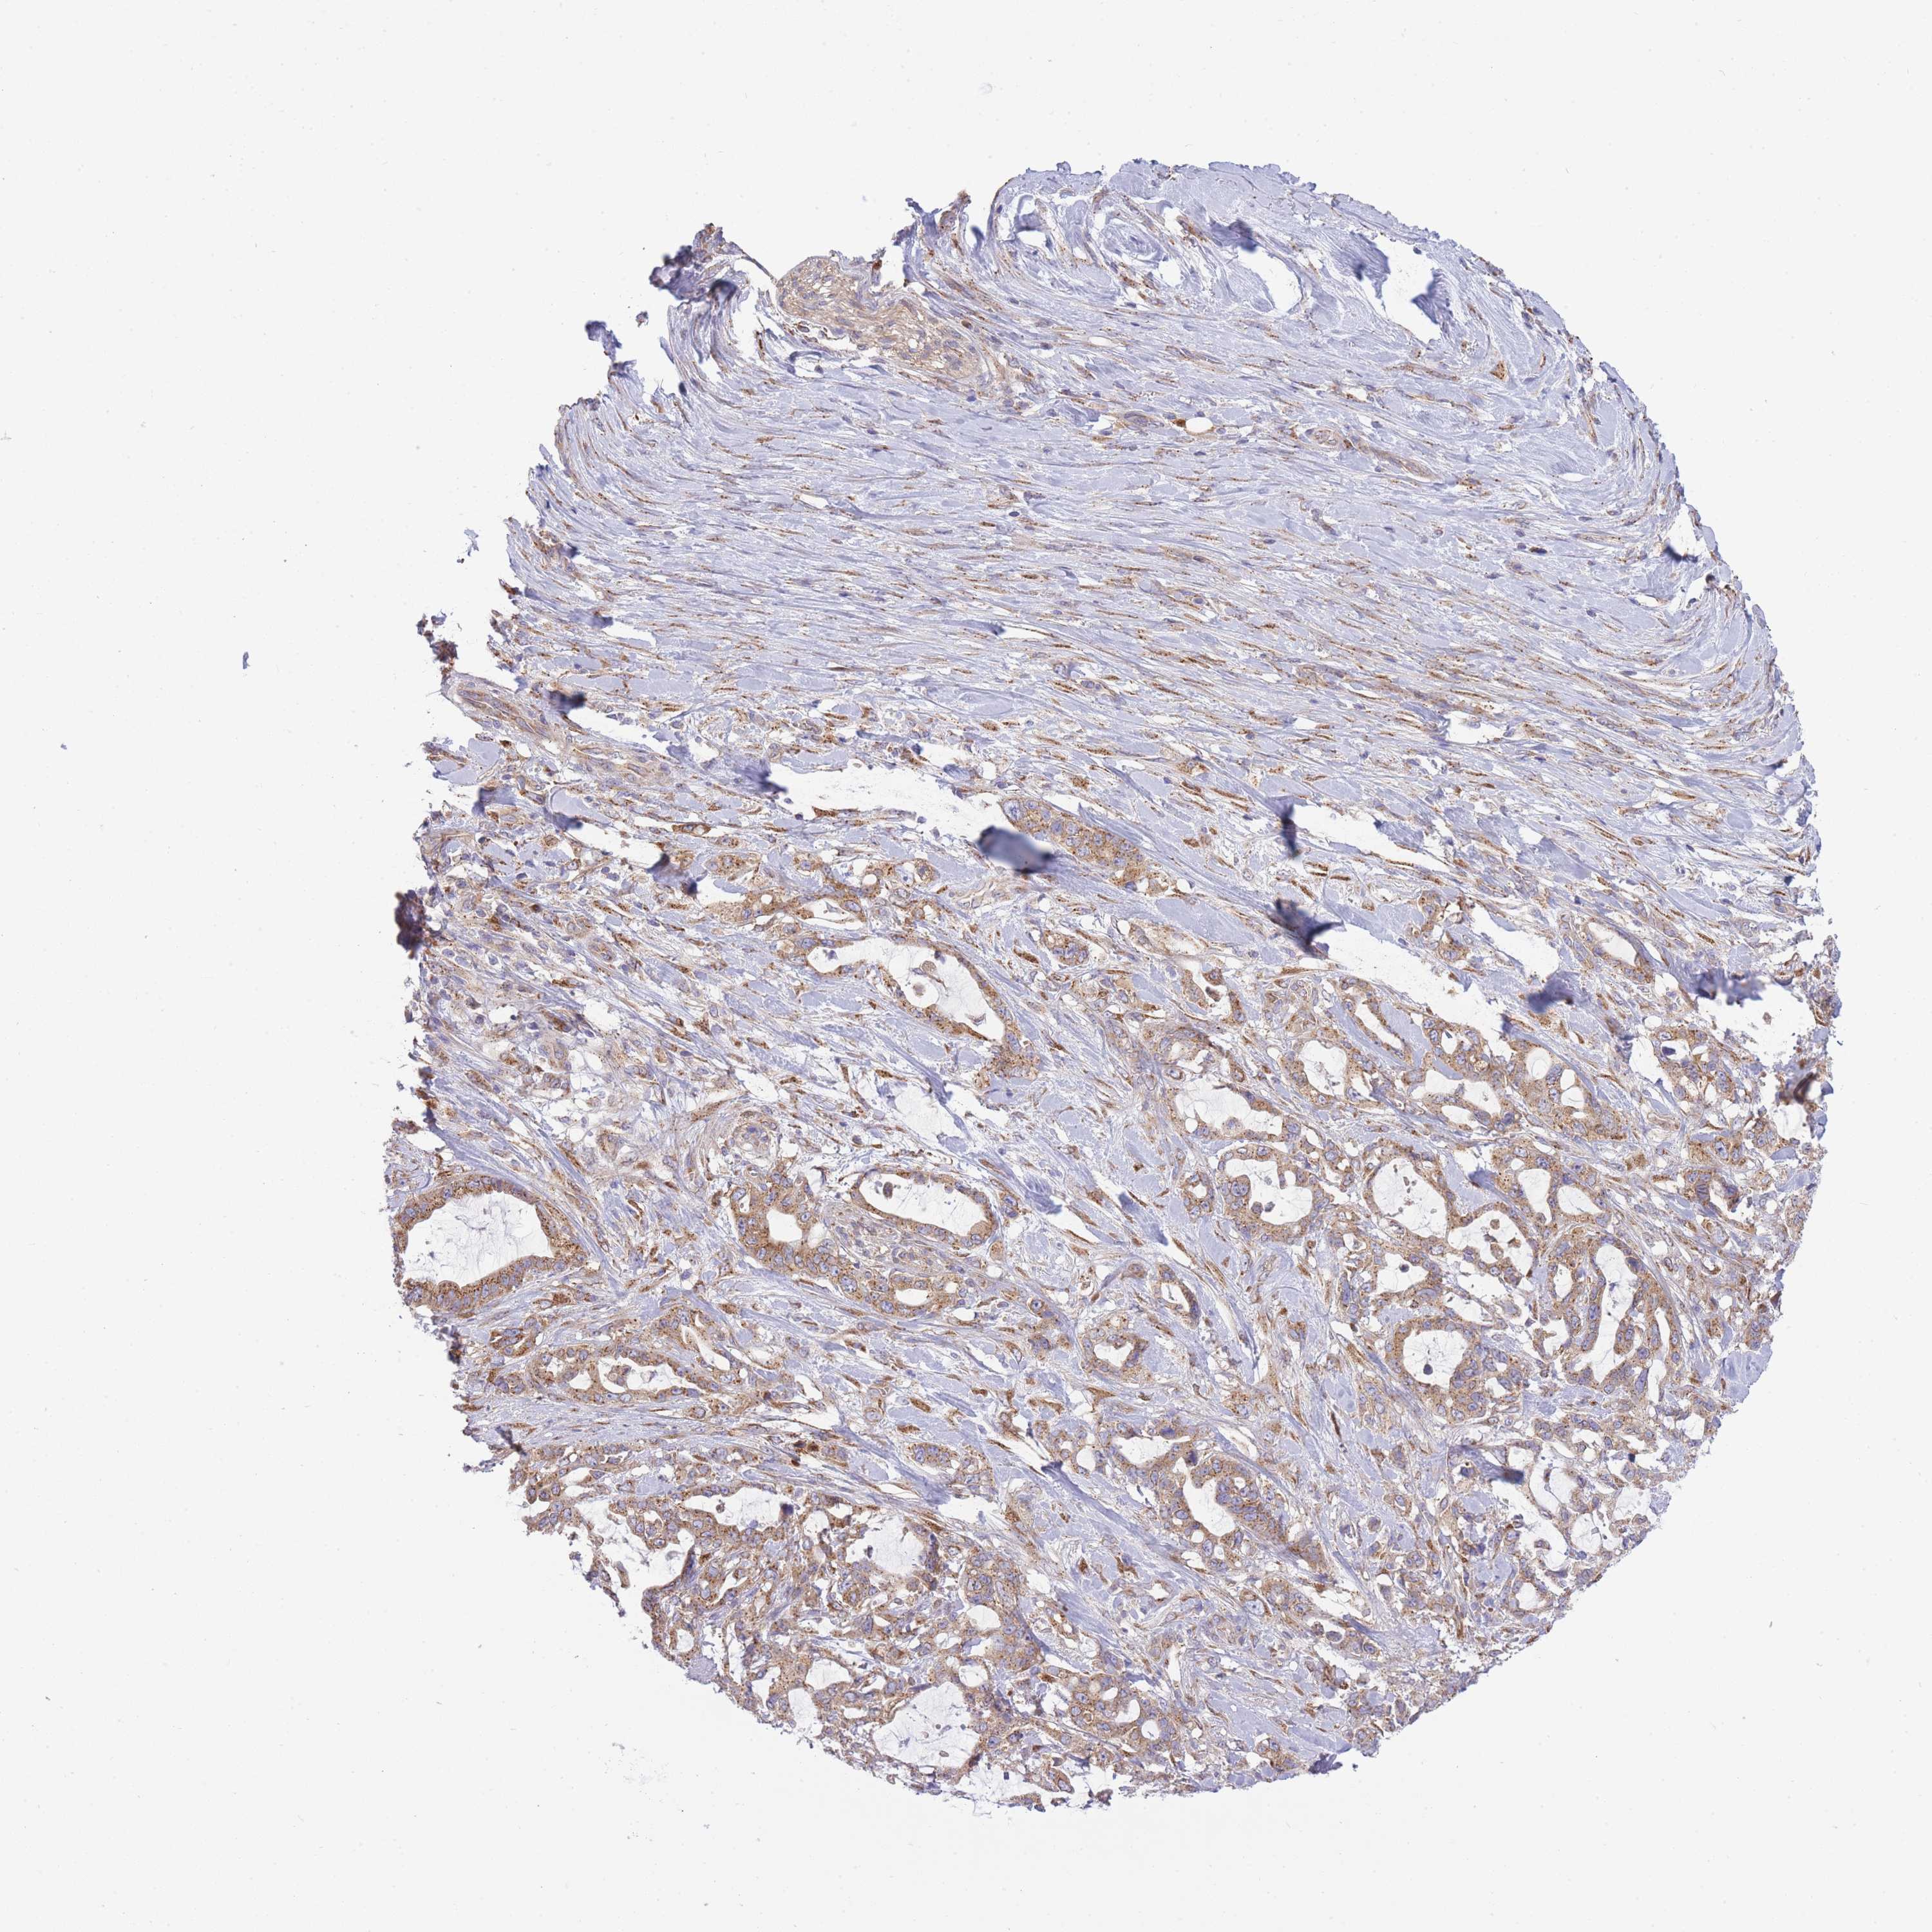

PANCREATIC CANCER - Protein expressioni

A mouse-over function shows sample information and annotation data. Click on an image to view it in a full screen mode. Samples can be filtered based on level of antibody staining by selecting one or several of the following categories: high, medium, low and not detected. The assay and annotation is described here.

Note that samples used for immunohistochemistry by the Human Protein Atlas do not correspond to samples in the TCGA dataset.

Antibody stainingi

Antibody staining in the annotated cell types in the current human tissue is reported as not detected, low, medium, or high, based on conventional immunohistochemistry profiling in selected tissues. This score is based on the combination of the staining intensity and fraction of stained cells.

Each image is clickable and will lead to virtual microscopy that enables deeper exploration of all samples and also displays staining intensity scores, fraction scores and subcellular localization as well as patient and tissue information for each sample.

Antibody HPA037866

Antibody HPA037867

Antibody HPA045712

Staining

High

Medium

Low

Not detected

Intensity

Strong

Moderate

Weak

Negative

Quantity

>75%

75%-25%

<25%

None

Location

Nuclear

Cytoplasmic/membranous

Cytoplasmic/membranous,nuclear

Adenocarcinoma, NOS